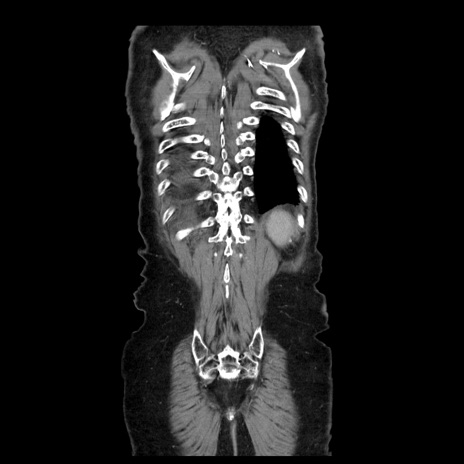

症例21(冠状断像)

【症例】70歳代男性

【主訴】腹痛

【現病歴】肝硬変・肝細胞癌にてかかりつけの方。約9時間前に食後より腹痛出現。症状が徐々に増悪し、嘔吐出現したため来院。

【既往歴】肝硬変、肝細胞癌(RFA、TACE後)

【身体所見】意識清明、表情苦悶様、BT 36℃、BP 129/78mmHg、P 88bpm、SpO2 97%(RA)、右上腹部から心窩部にかけて圧痛あり、反跳痛なし、筋性防御あり。

【データ】WBC 5800、CRP 0.16